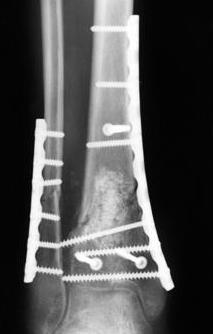

Уважаемые коллеги, остеосинтез малоберцовой кости при переломах пилона помогает решить, как минимум, 3 задачи:

1. шинировать сегмент. При переломах типа С, как правило, остеосинтез большеберцовой кости выполняется по спаданию отёка и заживлению мягких тканей, как и говорит об этом чуть ниже Djoldas. В этот период - с момента поступления пациента в стационар до собственно остеосинтеза перелома пилона мы можем стабилизировать конечность или путём остеосинтеза малоберцовой кости, или ExFix. Естественно, одно не равнозначно другому, для каждого метода есть свои показания в зависимости от характера перелома;

2. за счёт эффекта лигаментотаксиса восстановить правильные взаимоотношения в большеберцово-таранном сочленении. И действительно, я полностью согласен с Вами, Александр, такую же задачу мы решаем зачастую с помощью ExFix. И если наружная фиксация при переломе пилона является не методом первого этапа, а окончательным методом лечения перелома - ни о каком дополнительном остеосинтезе малоберцовой кости, как правило, речи не идёт и идти не должно. Но, если мы решили выполнить внутреннюю фиксацию, желательно помнить, что остеосинтез малоберцовой кости при переломе пилона помогает решить и ещё одну задачу - ортопедическую:

3. стабилизировать наружный опорный комплекс голени и предотвратить вальгусную деформацию голеностопного сустава. Конечно, данная проблема не очень актуальна, или вовсе не актуальна для 43С1, но для повреждений типа 43С2,3, особенно в случаях, когда метафизарный дефект потребовал пластики, а пластину пришлось уложить по медиальной стороне - остеосинтез малоберцовой кости является крайне необходимым - привожу характерный пример.

Но перелом малоберцовой кости может быть и много проксимальнее, и его так же приходится фиксировать из этих же соображений. И особенно, если пациент полный. Из отечественных хирургов на возможность развития такого осложнения - вальгусной деформации голеностопного сустава ч/з 2-3 месяца после операции при переломах типа 43С2 в отсутствии фиксации малоберцовой кости одним из первых указал Виталий Дрягин из ГКБ №3 Челябинска ещё в конце 90х.